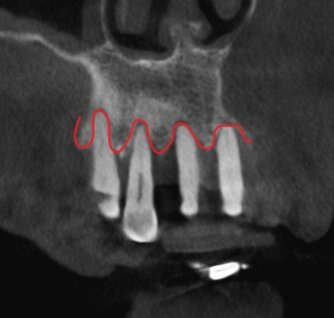

Боковой срез.

Сбоку - то же самое.